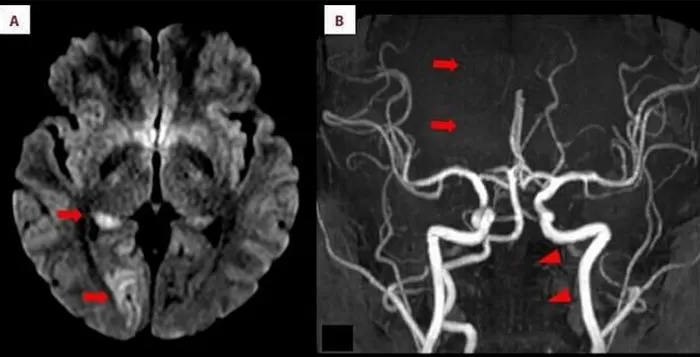

진단 결과는 충격적이었습니다. 격렬한 동작으로 인해 왼쪽 척추동맥 내막이 찢어지고, 이로 인해 혈액이 스며들어 혈전이 형성되었다는 것입니다.

이 혈전이 뇌 시각 중추로 가는 주요 혈관을 막아 허혈성 뇌졸중(뇌경색)을 유발했습니다.

인사이트 American Journal of Case Reports

결과적으로 A씨는 양쪽 눈의 왼쪽 반쪽 시야를 잃고 왼쪽 반신 감각을 상실하는 심각한 상태에 이르렀습니다.

다행히도 의료진은 신속하게 대응했습니다. 대퇴동맥 카테터 삽입을 통한 혈전 제거 수술과 국소 혈전 용해 치료를 병행해 혈류를 성공적으로 회복시켰습니다.